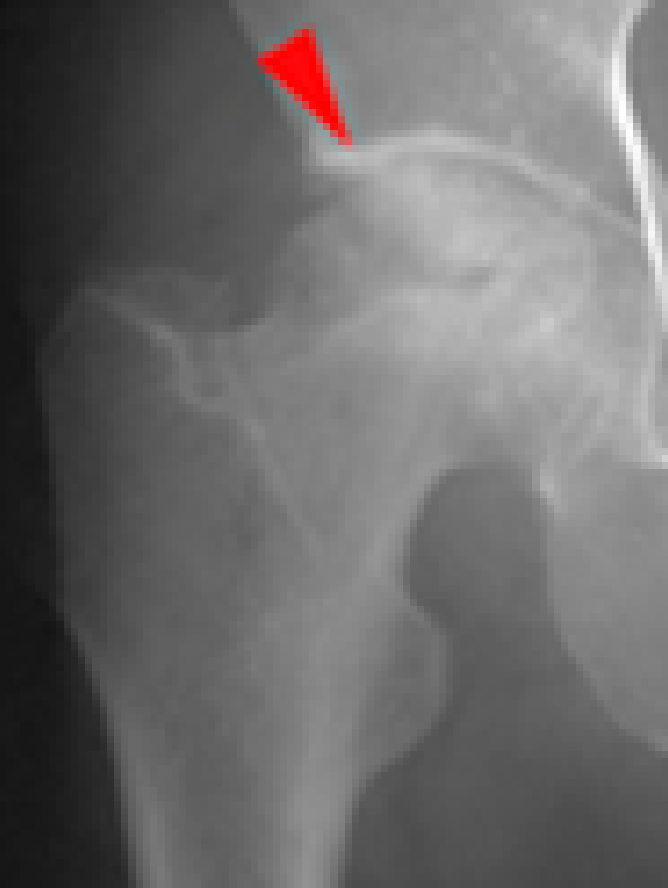

主な股関節症には、変形性股関節症(図4)、大腿骨頭壊死症(図5)、関節リウマチ(図6)などがあります。

図5. 大腿骨頭壊死症

(赤矢印が骨頭壊死部分)

5. 大腿骨頭壊死症

大腿骨頭壊死症は、大腿骨頭への血流障害によって股関節が破壊される病気で(図9赤矢印)原因は分かっておらず難病指定されています。しかし、ステロイド剤を多量に使用したパルス療法やアルコール多飲歴の有る方に多く発症しやすい傾向があります。

図9. 代替骨頭壊死症(赤矢印が壊死部分)